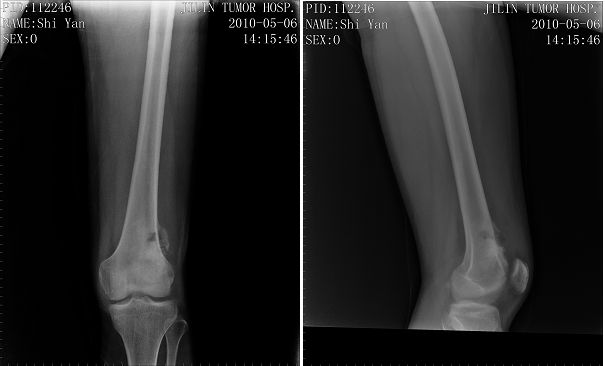

右侧股骨下端骨肿瘤,行右股骨下端骨肉瘤瘤段切除、人工假体置换术。现右膝关节可屈曲至90度,行走自如。